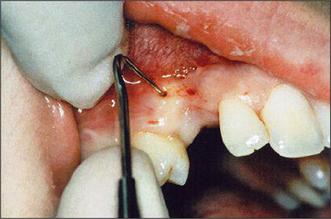

Other anatomical structures may become more prominent with tooth loss. The genial tubercles and their muscle attachments may become prominent in a patient with extensive resorption of the mandible, sometimes compromising denture stability. Maxillary or mandibular tori may also cause instability of a denture, or may be traumatized by it. A prominent fraenum (Fig. 11.3) can displace a denture during function, and may weaken the denture base so that it fractures through flexing.

Fig. 11.3 A prominent labial fraenum causes displacement of the denture. If the denture flange is eased to fit round the fraenum, the denture may be weakened. Excision of the fraenum (fraenectomy) is indicated.

Prominent labial fraenum

The flange of a denture may traumatize a prominent labial fraenum or muscle attachment (Fig. 11.3). If the fraenum is relatively small, this may be managed by trimming back the labial or lingual denture flange. However, the denture may be weakened and it might fracture if extensive trimming is undertaken to relieve the fraenum. Excision of the fraenum (fraenectomy) may be indicated to avoid this.